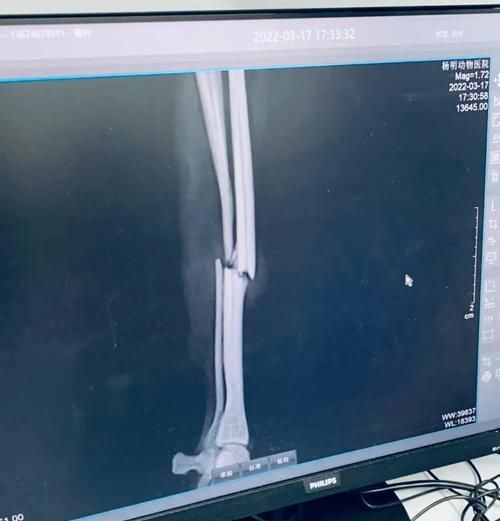

6.骨折类型与康复时间的关系:不同类型的骨折,康复时间也各不相同。

8.骨折部位对康复时间的影响:不同部位的骨折需要不同的康复时间。

14.骨折幼犬康复时间的预估:根据骨折类型和部位,一般需要4至8周的时间。